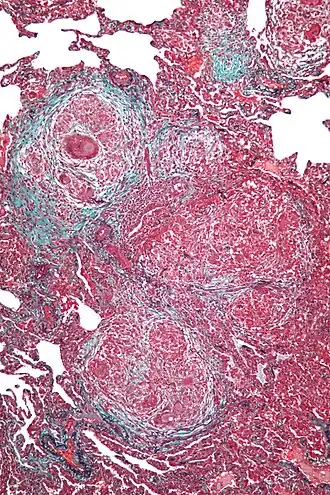

В конце XIX века Роберт Кох впервые наблюдал гиперчувствительность замедленного типа при введении туберкулёзных бацилл в кожу зараженного туберкулёзом животного. Такая инъекция через 1-2 суток вызывала местное воспаление с образованием гранул. В свою очередь, у здоровых животных реакция была слабой и кратковременной.